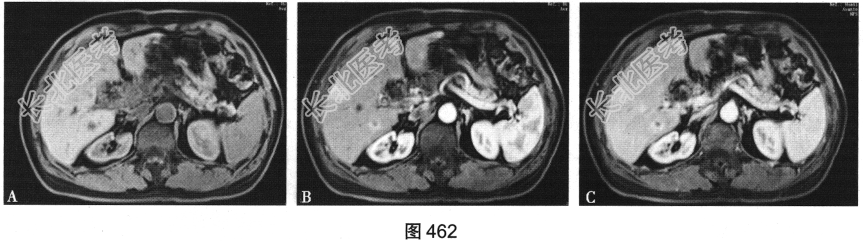

- 多项选择题6.[提示]患者术后半年复查MRI,如图462所示。患者可能的诊断是( )

A、局部复发

B、淋巴结转移

C、未见转移

D、脾脏转移

E、胆肠吻合口漏

F、胰腺转移

G、肾脏转移

H、肝脏转移

I、局部未见复发

关注下方微信公众号,搜题查看答案

- 多项选择题7.根据术后MRI图,转移灶位于何处( )

A、尾状叶

B、脾脏

C、肝左内叶

D、肝左外叶

E、腹主动脉旁

F、肝右前叶

G、左肾

H、肝右后叶

I、胰腺

J、右肾